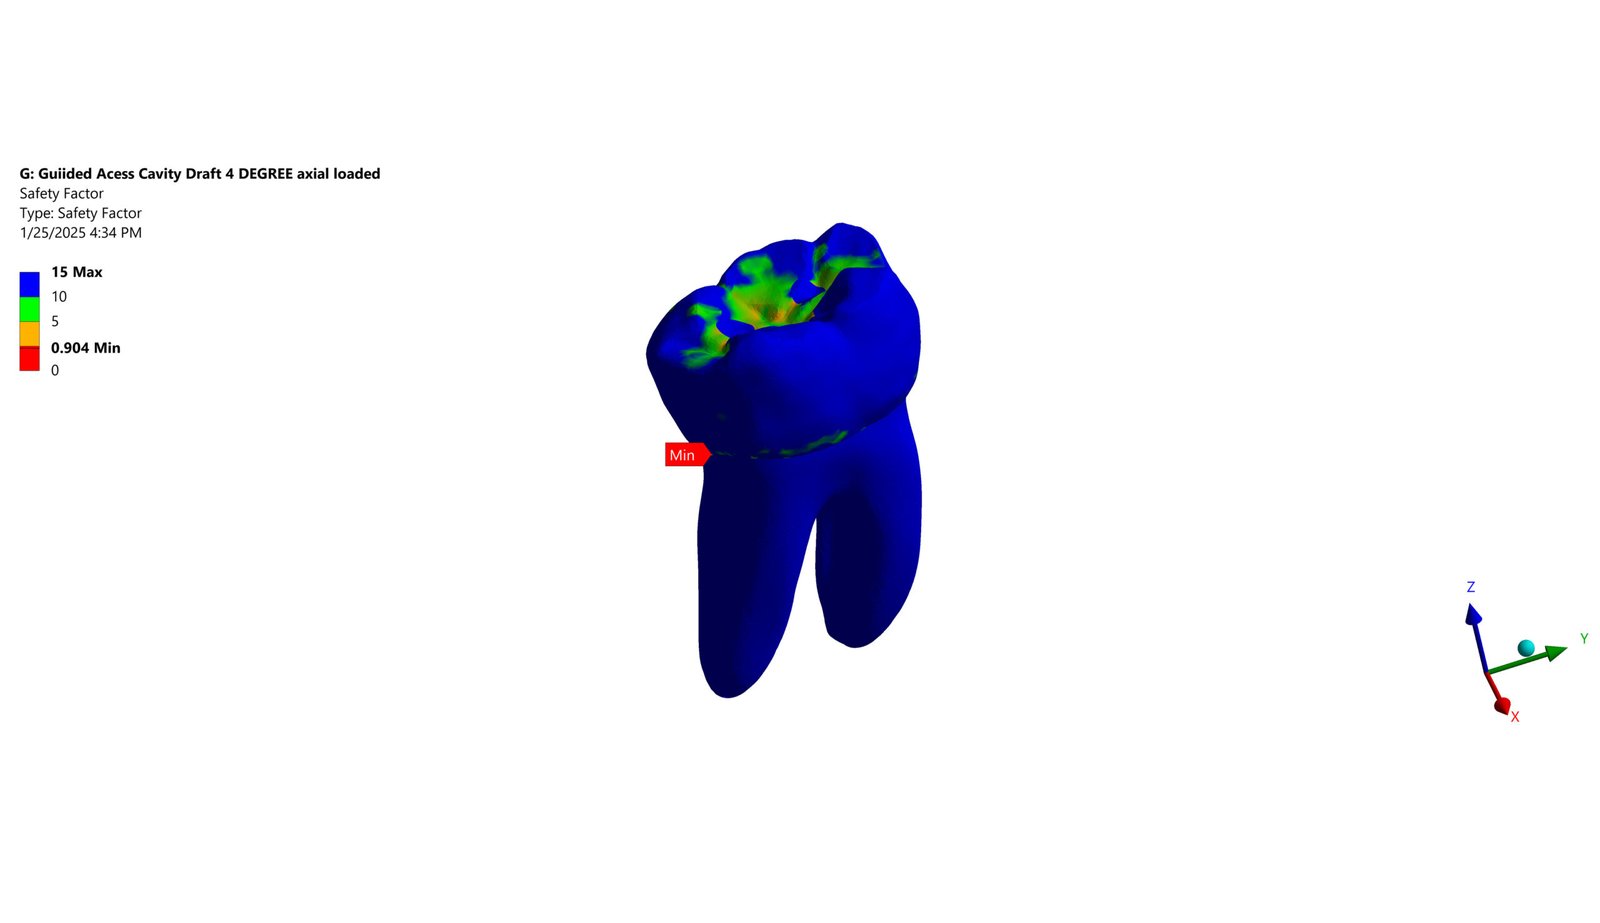

The Endodontic FEA section evaluates the biomechanical performance of root canal–treated teeth, endodontic tools, and reinforcement strategies. Through precise material characterization and micro-CT–based superimposition, we assess fracture risk, stress pathways, and instrument fatigue under various clinical scenarios. These simulations guide the selection of safer instrumentation techniques and restorative strategies. Our goal is to enhance predictability and reduce procedural complications.